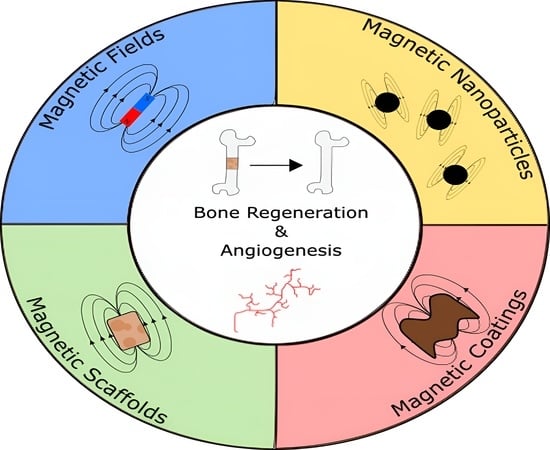

Magnetic Bone Tissue Engineering: Reviewing the Effects of Magnetic Stimulation on Bone Regeneration and Angiogenesis

Abstract

1. Introduction

2. Magnetic Fields Influence on Cell Behaviour

2.1. Influence of Magnetic Stimulation on Bone Regeneration

2.2. Influence of Magnetic Stimulation on Angiogenesis

3. Magnetic Nanoparticles Influence on Cell Behavior

4. Magnetic Scaffolds in Bone Tissue Engineering

5. Magnetic Coatings in Bone Tissue Engineering